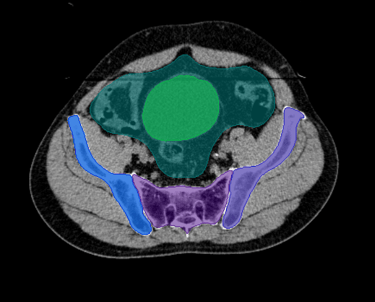

O SegmentaR foca na segmentação automática das três regiões fundamentais para o planejamento de radioterapia: cabeça e pescoço, tórax e pelve. Essas são as regiões essenciais que todo profissional precisa para uma segmentação precisa e eficiente.

Pelve

Bexiga

Bulbo Peniano

Cauda Equina

Sacro

Fêmur Esquerdo

Fêmur Direito

Bolsa Intestinal

Reto

Ilíaco Direito

Ilíaco Esquerdo

Sínfise Púbica

Rim Esquerdo

Rim Direito